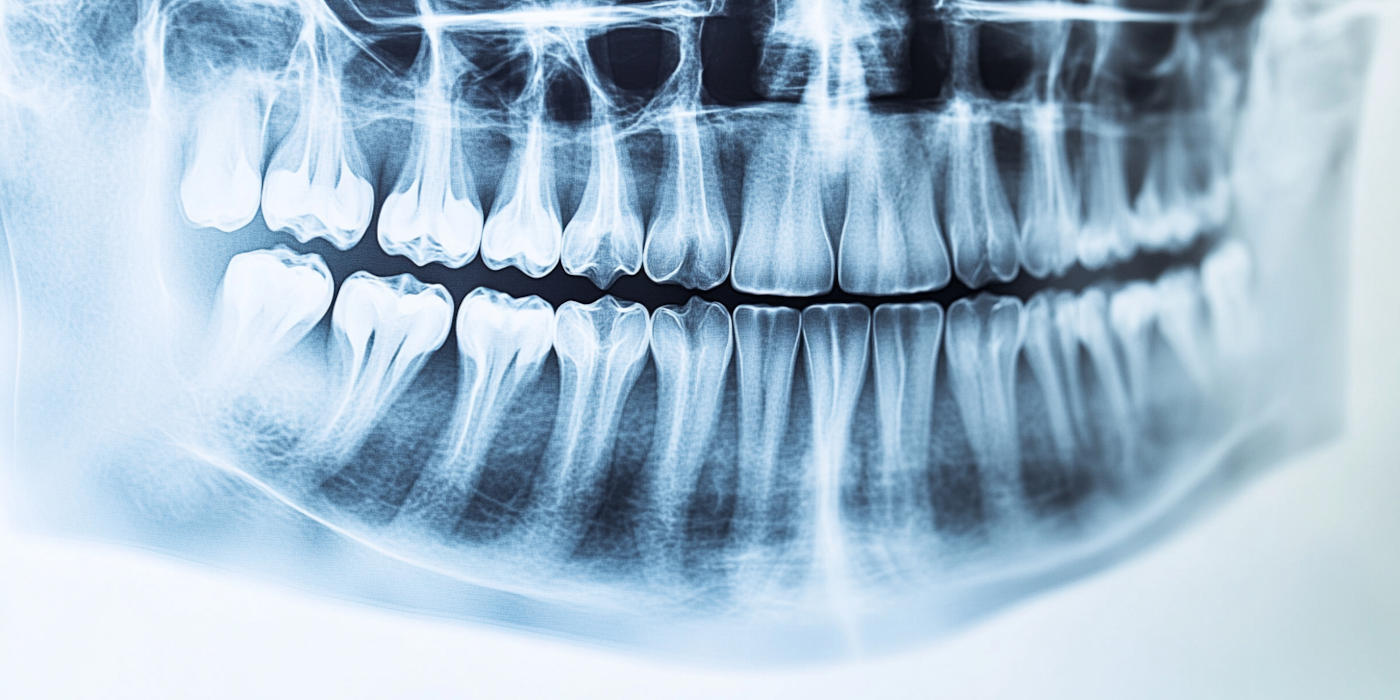

🦷 Traitement endodontique (dévitalisation)

Lorsque l’infection atteint le nerf de la dent, un traitement endodontique est nécessaire.

Il consiste à nettoyer et désinfecter l’intérieur de la dent afin d’éliminer la douleur et l’infection.

👉 Réalisé sous anesthésie, ce soin permet de soulager rapidement la douleur et de conserver la dent.